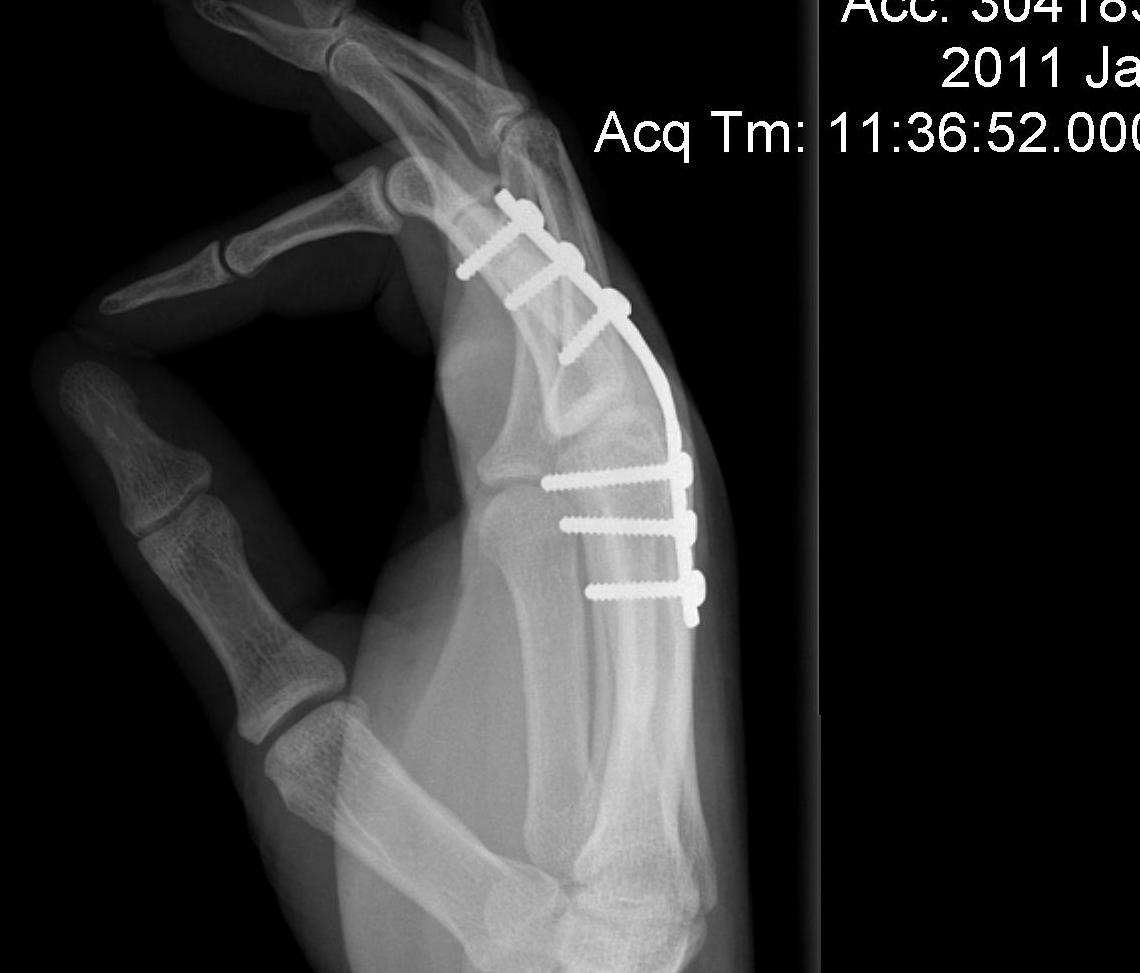

Type III bicondylar fractures

- difficult fractures

- 90 degree condylar plate

- lag screw and plate

- high risk of joint stiffness